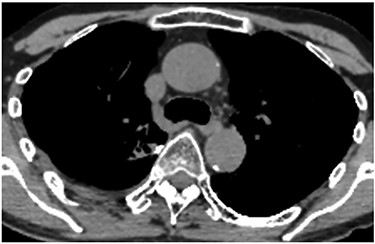

A 60-year-old man underwent right apical and posterior segmentectomies via VATS for early-stage lung cancer. The bronchus and pulmonary parenchyma were divided by endoscopic staples (Echelon®; Ethicon Endo-Surgery). The resected tumour was 1.5 cm in the longest diameter and pathologically diagnosed as Stage IA adenocarcinoma. The patient was discharged uneventfully on eighth day after surgery. Chest radiography revealed no significant findings, and laboratory data were within the normal ranges on the 14th day after discharge at a scheduled visit to the outpatient clinic. However, the patient was transported by ambulance to our hospital owing to a sudden onset of chest pain and dyspnoea on the 32nd day after discharge. He developed hypotension and tachycardia with systolic blood pressure of 50 mmHg and heart rate of 114 beats/min. The haemoglobin concentration level, which had been 12.3 mg/dl on the 14th day after discharge, decreased by 8.7 mg/dl. Chest radiography revealed a massive right pleural fluid, and enhanced computed tomography (CT) showed an extravasation of contrast media near the fifth thoracic vertebra (Fig. 1). The patient was diagnosed with haemothorax and an emergency operation was performed. Thoracoscopic examination revealed massive blood coagulation in the right thoracic cavity, with no adhesions. After removal of the coagulation, continuous active bleeding from the intercostal artery was found near the fifth thoracic vertebra in the vicinity of a stump of the bronchus divided by a staple (Supplementary Video 1). A thoracotomy through the fifth intercostal space was therefore performed to achieve haemostasis, and the bleeding was stopped by suturing using a 4–0 nonabsorbable monofilament ligature. In addition, the bleeding point was covered with a collagen-fibrin patch (Tachosil®). The posterior part of the staple line of the lung parenchyma adjacent to the bleeding point under full inflation was partly exposed, whereas the bronchial stump was covered with lung. Therefore, the scratching created by the staples was assumed to cause haemothorax. The total amount of haematoma in the right thoracic cavity and the intraoperative blood loss was 3980 g. Postoperative CT confirmed that the stapler dividing the lung parenchyma directly faced the bleeding point beside the fifth vertebra (Fig. 2). The patient progressed satisfactorily after the reoperation and was discharged on ninth day after reoperation.

Postoperative CT revealing that the stapler dividing the lung parenchyma directly touched the fifth vertebra (arrow).

VATS is now a mainstay for the diagnosis and treatment of thoracic disease, and the mechanical stapler has become a reliable tool during VATS procedures. Staple-associated haemothorax, however, should be recognized as a life-threatening complication after VATS procedures. Staples with reinforcement material (Duet TRS®; Covidien) have been reported to possess the potential to cause serious haemothorax by scratching the inner chest wall. Kanai and colleagues reported massive haemothorax occurring on the first day after thoracoscopic lung biopsy for idiopathic interstitial pneumonia using a staple with reinforcement material [1]. In their case, during emergency reoperation, active bleeding from the intercostal artery was identified, which was suspected to be instigated by the sharp edge of the reinforcement material on the crossing point of the double endostapling. This product was voluntarily recalled by the maker after 13 serious injuries and three fatalities were reported after being applied in the thoracic cavity [4]. The incidence of haemothorax induced by ordinary staples without reinforced material is extremely rare. There are only two reports describing such a complication when literature is searched using the key words ‘haemothorax’, ‘pulmonary resection’ and ‘stapler’ on PubMed. One report described haemorrhage from the internal thoracic artery that occurred on the 12th day after VATS right upper lobectomy [2]. Another report revealed haemothorax caused by bleeding from the intercostal artery, which faced a stump of the right lower vein divided by a staple on the 11th day after VATS lobectomy [3]. Both of these cases were of sudden onset and required an emergency operation because of haemorrhagic shock. In these cases, the cause of the haemothorax was assumed to be the end of the staple line protruding and incidentally injuring the artery. Haemothorax after VATS is explained by the following scenario. The VATS procedure, which usually uses the mechanical stapler, leads to less postoperative pain and enables patient’s full respiratory movement including cough, although the staple line can scratch adjacent organs and chest wall during the respiratory movement. Furthermore, the VATS procedure is less likely to induce pleural adhesion than thoracotomy because of the lesser invasion of parietal pleura. In our case, intraoperative findings showed no pleural adhesion even on the 40th day after surgery and the stapling line then moved dramatically, synchronizing with respiratory movement and scratching the bleeding point, as revealed on the postoperative CT.